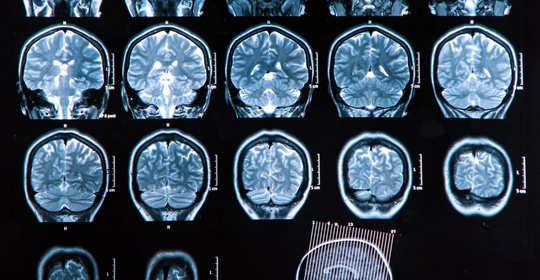

硬腦膜膿腫:症狀、診斷與治療

硬腦膜膿腫:診斷與治療方法

硬腦膜膿腫:頸椎硬膜外膿瘍與脊髓椎管炎的鑑別與治療

硬腦膜膿腫:病因、症狀及治療方法